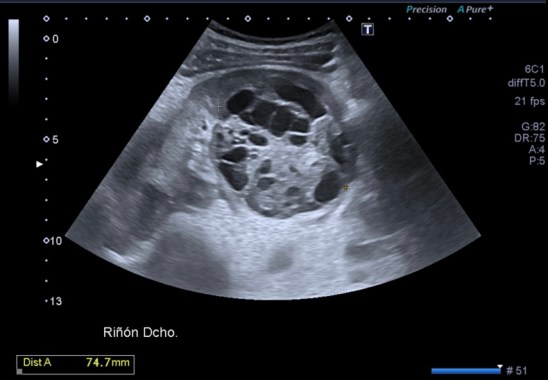

Lesión heterogénea, en el meso-riñón derecho, redonda, típica de quiste hidatídico.

Después de ver esta maravilla de imágenes, habiendo repasado el post 262 donde te explico las claves del quiste hidatídico, no tengo nada más que decir. Las imágenes hablan por si mismas. Perfectas, con una calidad increíble, el equipo increíble, bien ajustado, los parámetros adecuados, es un estudio perfecto, Sandra…yo lo sabía y te lo decía y estoy orgulloso, muy orgulloso de hacer esto que estoy haciendo ahora, en el día 2.

Un quiste hidatídico renal, maravilloso.